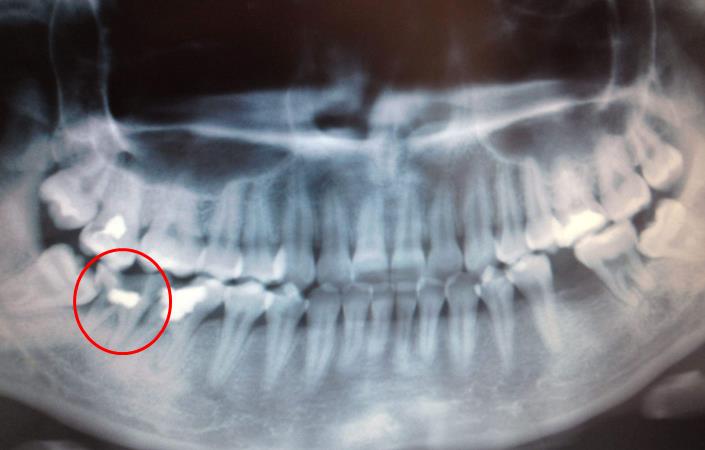

2、口腔全景片怎麽(me) 看有沒有蛀牙

一般來說,常見的蛀牙通常可以通過牙片發現,尤其是齲壞比較多(如下圖),在牙片上會(hui) 出現黑色陰影的缺損,但是如果是鄰麵齲以及齲壞程度等通常就需要到醫院醫生用探針、口鏡等進行檢查確定。

智齒鄰牙蛀牙